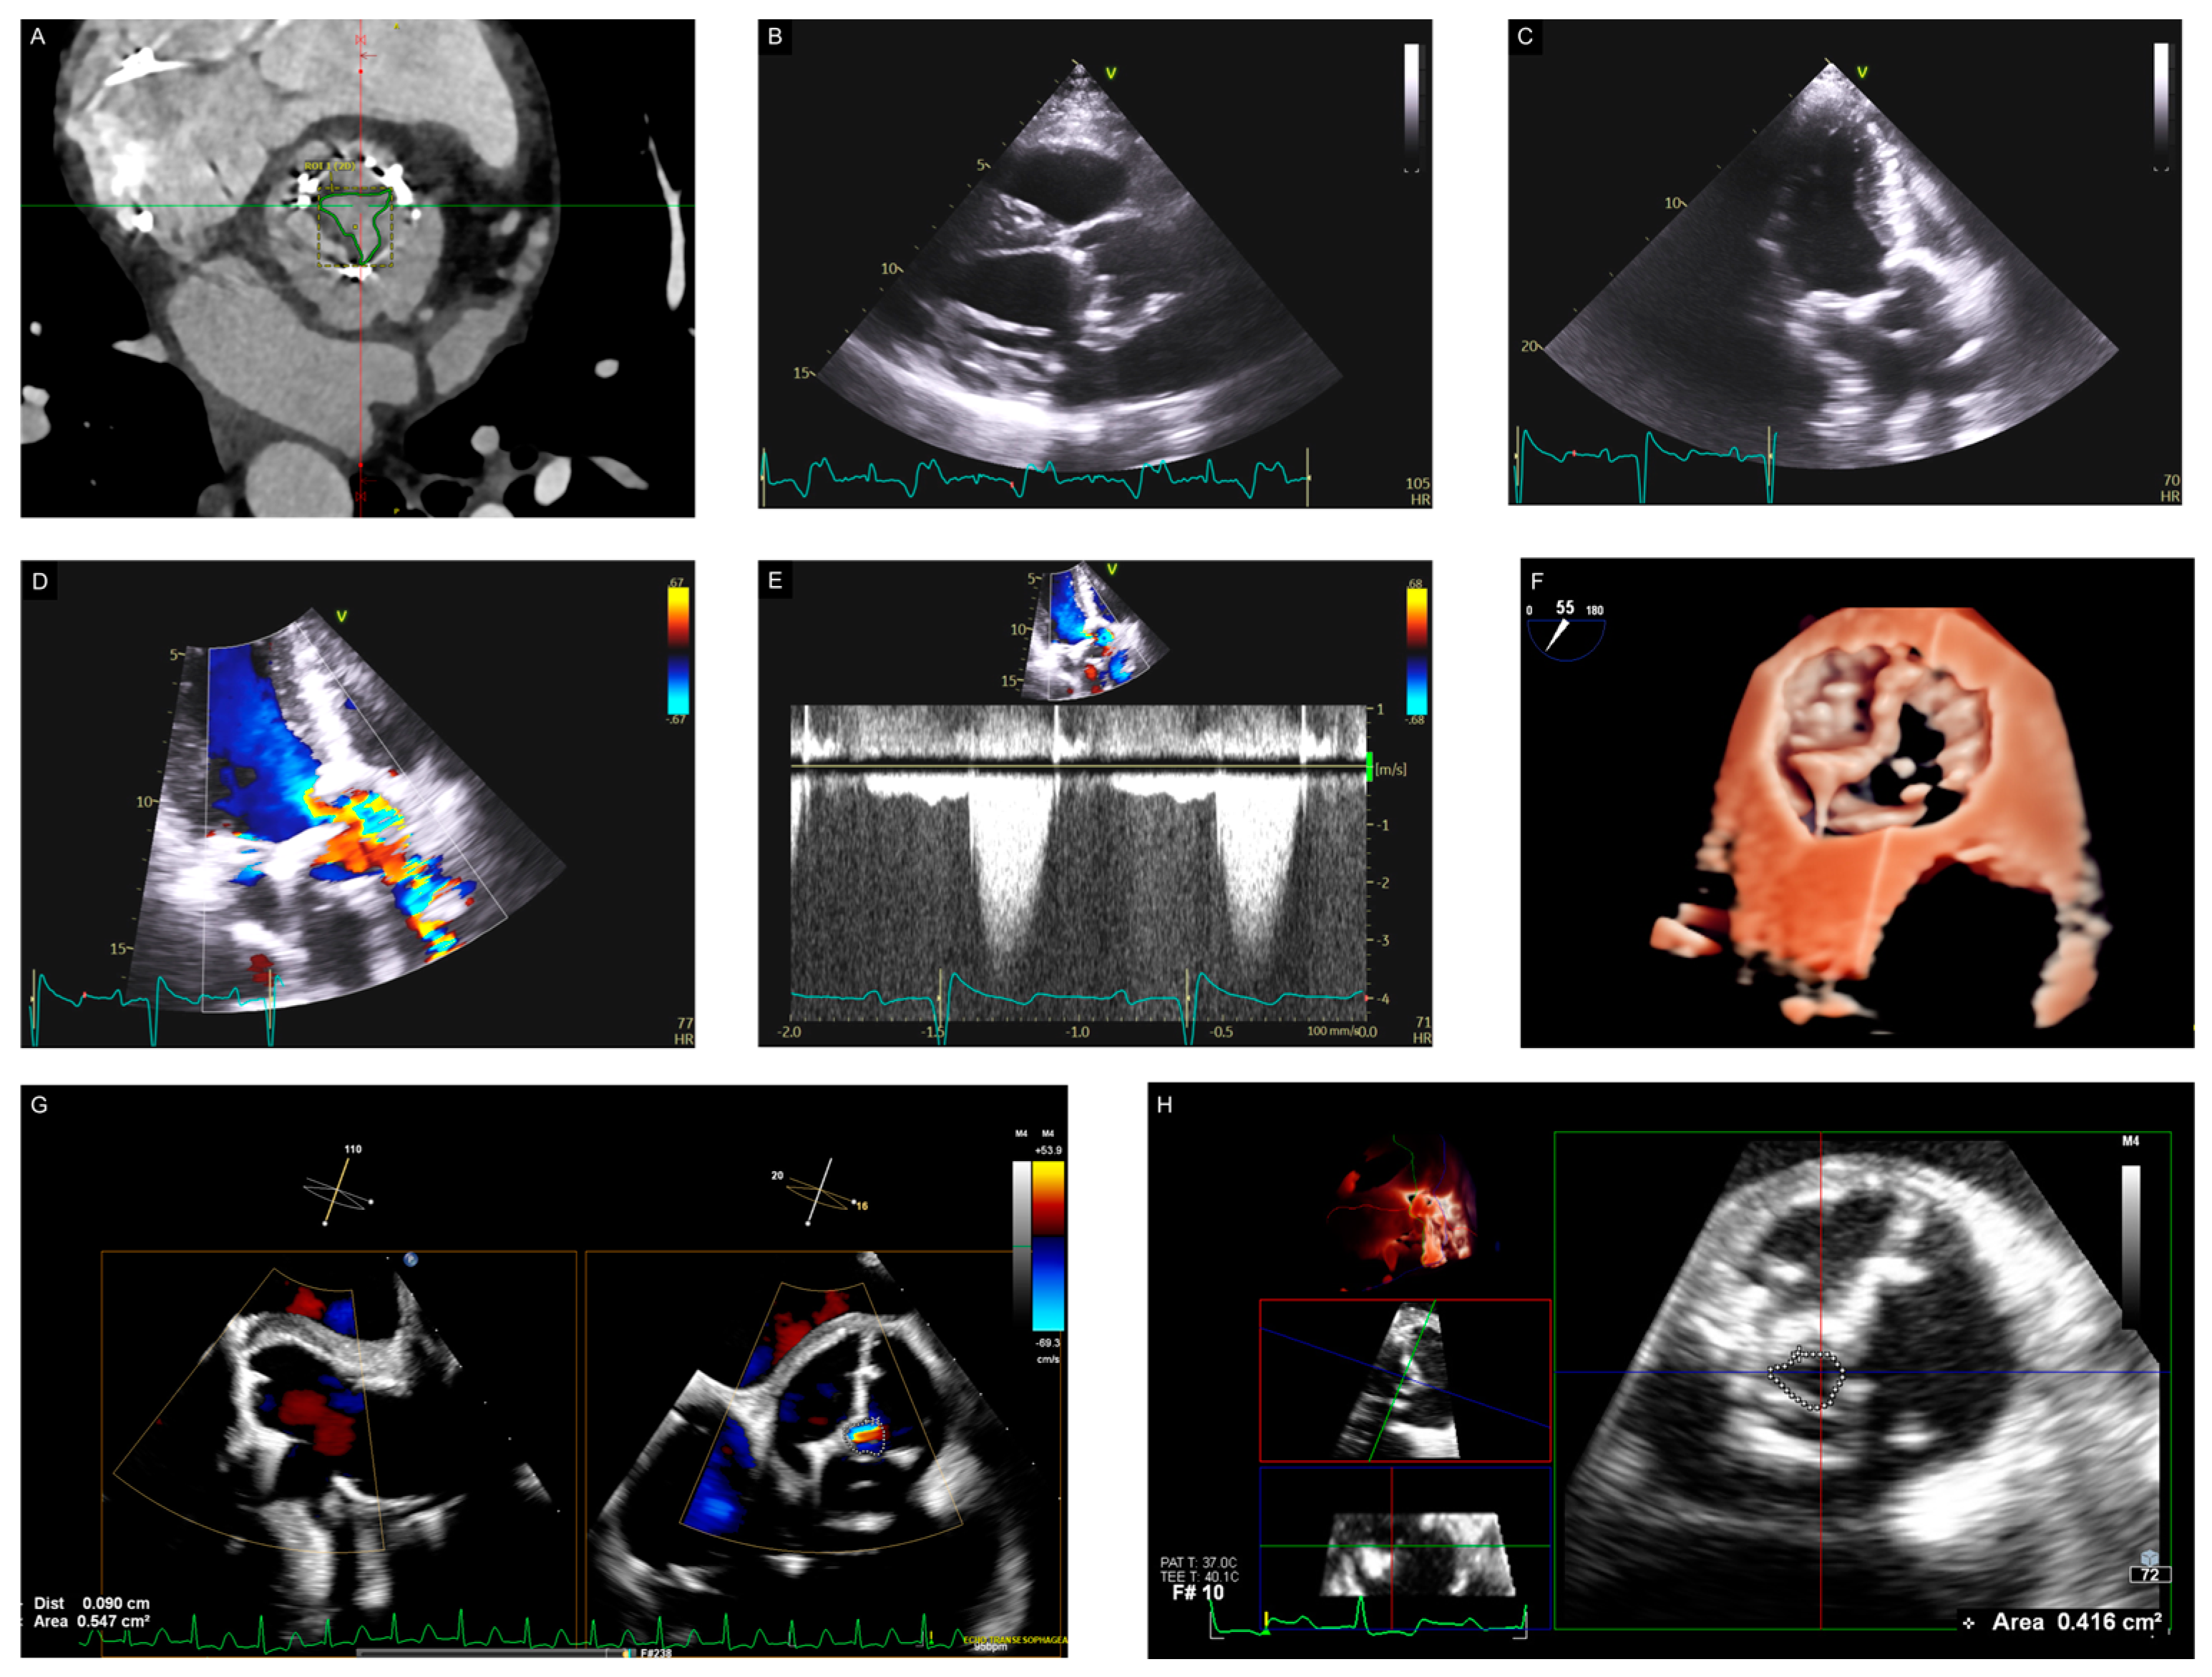

- Mirsadraee, S.; Sellers, S.; Duncan, A.; Hamadanchi, A.; Gorog, D.A. Bioprosthetic valve thrombosis and degeneration following transcatheter aortic valve implantation (TAVI). Clin. Radiol. 2021, 76, 73.e39–73.e47. [Google Scholar] [CrossRef]

- Andrews, J.P.M.; Cartlidge, T.R.; Dweck, M.R.; Moss, A.J. Cardiac CT in prosthetic aortic valve complications. Br. J. Radiol. 2019, 92, 20180237. [Google Scholar] [CrossRef] [PubMed]

- Sellers, S.L.; Blanke, P.; Leipsic, J.A. Bioprosthetic Heart Valve Degeneration and Dysfunction: Focus on Mechanisms and Multidisciplinary Imaging Considerations. Radiol. Cardiothorac. Imaging 2019, 1, e190004. [Google Scholar] [CrossRef] [PubMed]